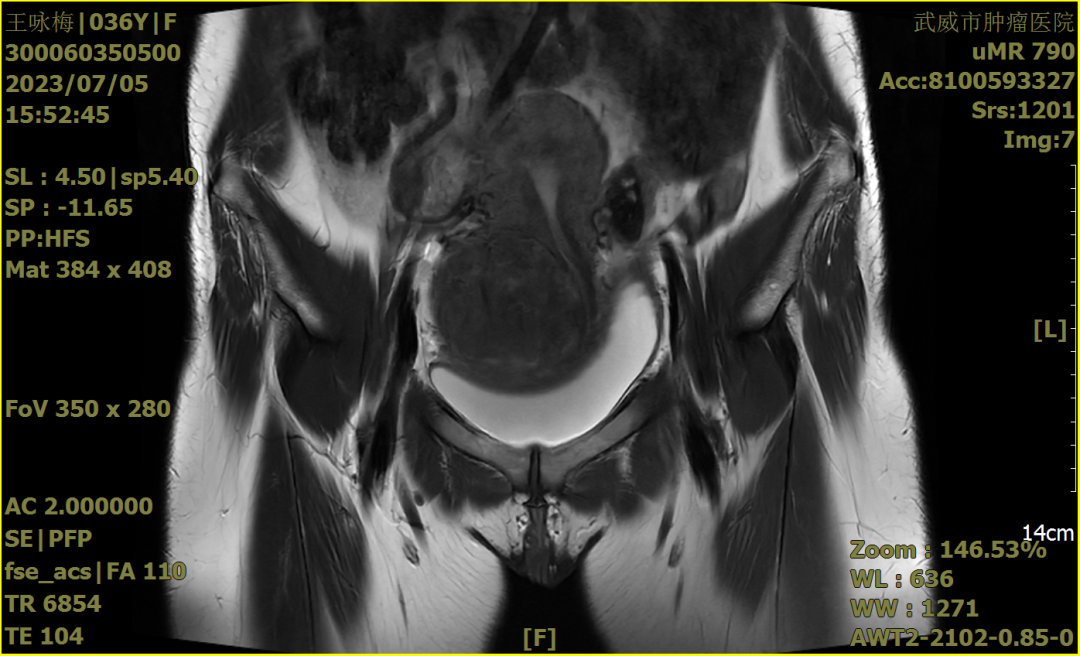

手术前我们再次确认患者的HPV检测阴性;宫颈TCT涂片:无上皮内病变或恶性病变(NILM)。血常规、肝功能、肾功能、心功能、肺功能等均无明显异常。B超、核磁共振检查(如下图)。

2023-7-5盆腔核磁(冠状位)

2022年7月8日栾桦主任带领我院王睿梅主任的妇科团队,在肚子上打了4个小孔,花了将近5小时的时间,用腹腔镜成功完成了王女士的肌瘤剔除手术,术中确认为宫颈中央型肌瘤,瘤体包围宫颈前壁、后壁及右侧壁,大小约11*10*10cm,术中边剔除边止血,尽可能的减少出血,因瘤体太大,压迫到右侧输尿管,为避免和预防术后输尿管瘘的发生,我们特意邀请泌尿外科协助放置了双侧输尿管J型导管。术后患者无任何手术并发症,术后病理提示子宫颈平滑肌瘤,术后8天王女士康复出院。